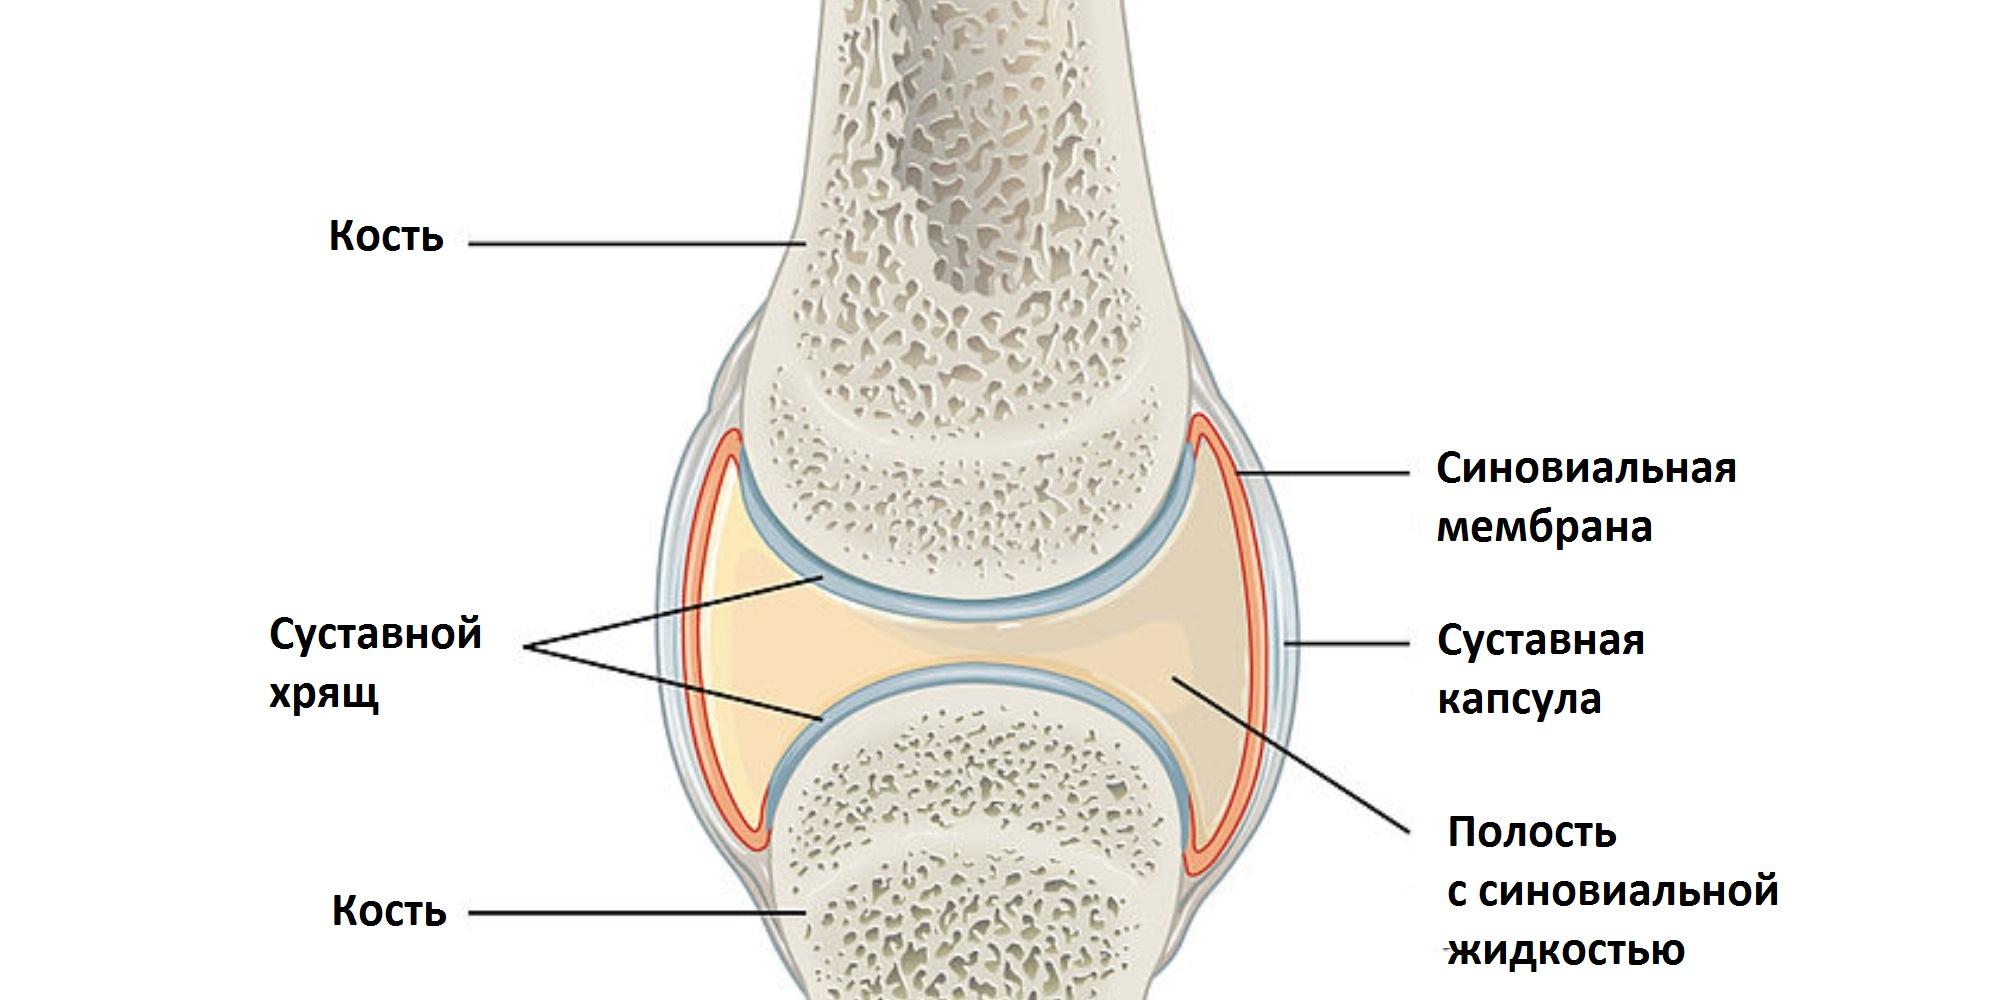

Рисунки Суставов: Анатомические Иллюстрации